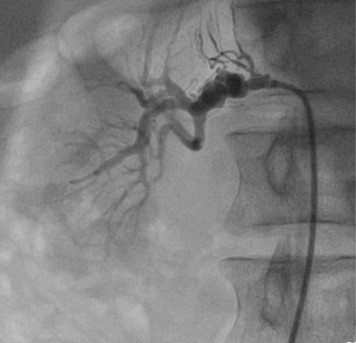

Renal angiogram :

Most probably Fibromusclar dysplasia because angiogram shows beaded appearance of the RT renal artery.

the renal angiogram shows beaded shaped right renal artery which is a finding of fibromuscular dysplasia (FMD)of the right renal artery